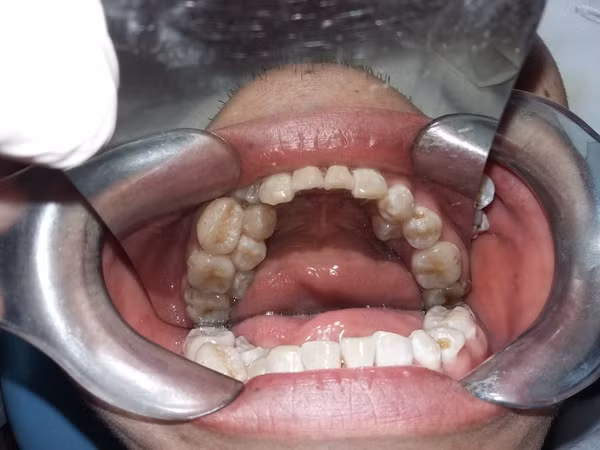

Ngày 20-6, bác sĩ Nguyễn Thị Thanh Châm, khoa Phẫu thuật Tạo hình Hàm mặt, Bệnh viện Việt Nam- Cu Ba cho biết, bệnh nhân Văn Sơn (28 tuổi) đến bệnh viện khám vì thấy đau nhức răng ở hàm trên bên trái. Tuy nhiên, qua thăm khám, các bác sĩ vô cùng bất ngờ khi phát hiện bệnh nhân mọc thừa 13 chiếc răng, cộng thêm 4 chiếc răng khác ở hàm dưới đang nhú.

Bệnh nhân mọc thừa tới 13 chiếc răng, cộng thêm 4 chiếc răng nữa đang nhú

Cụ thể, bệnh nhân mọc thừa đến 13 chiếc răng số 4 và 5 trên 2 hàm- răng hàm nhỏ. Các răng mọc lệch, chen chúc, khó vệ sinh, cặn thức ăn dính vào kẽ lâu ngày tạo thành các mảng bám, một răng bị sâu viêm tủy khiến bệnh nhân đau nhức khó chịu. Đây là trường hợp mọc thừa răng nhiều nhất bác sĩ từng gặp.